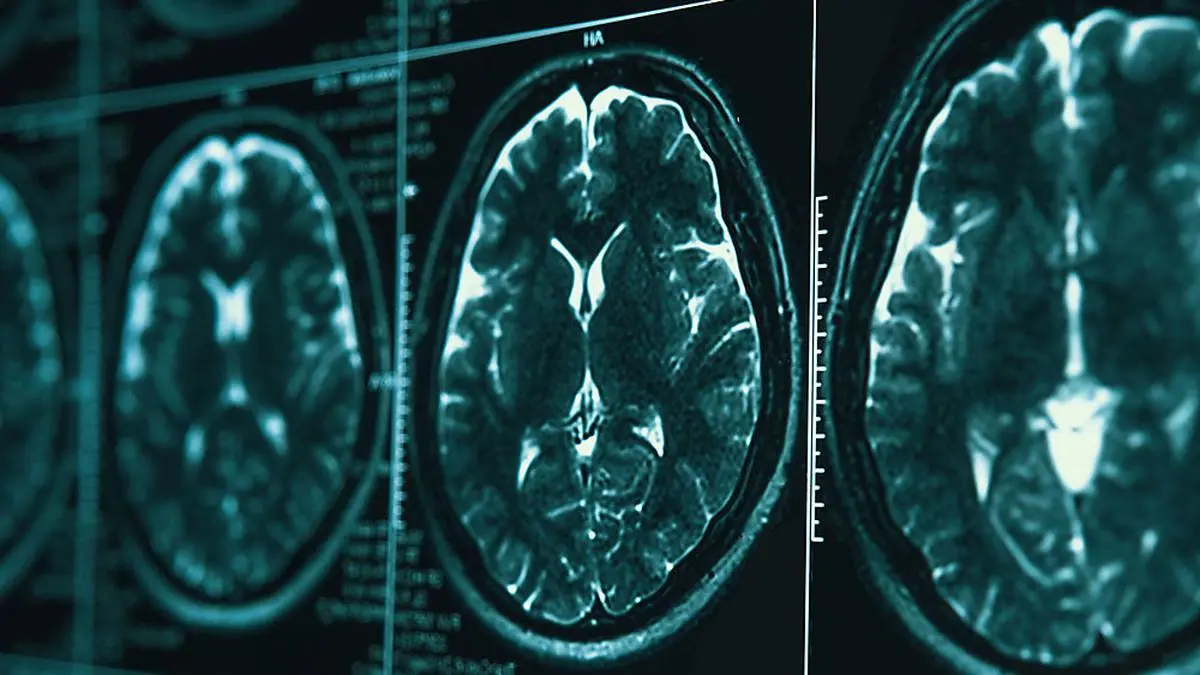

''Schrumpfung des Gehirns''

Covid-19-Infektion kann Gehirnschäden verursachen

Hirnscans zeigen, dass eine Covid-Erkrankung auch Auswirkungen auf das Gehirn haben kann. Ob die Veränderungen temporär sind und sich auch wieder rückbilden, muss nun erforscht werden.